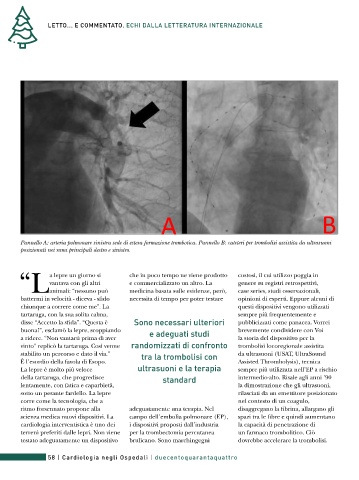

Pannello A: arteria polmonare sinistra sede di estesa formazione trombotica. Pannello B: cateteri per trombolisi assistita da ultrasuoni

posizionati nei rami principali destro e sinistro.